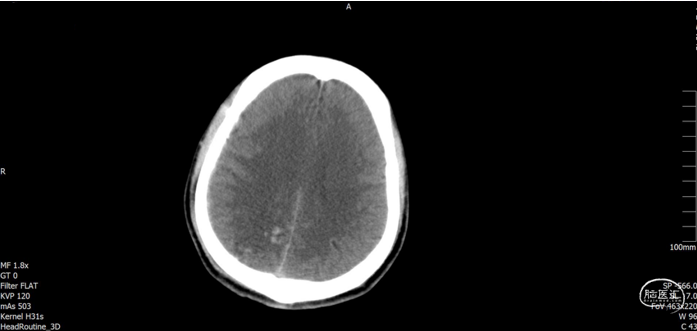

术后随访

术后72h CT,复查后拔除硬膜下引流管

术后72h胸部 CT

术后1周 CT

术后70天CT